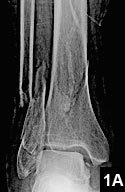

We also have the capability to take x-ray in office. So patients with minor or moderate trauma- such as ankle fractures- can have full range of treatment without the hospital visit.